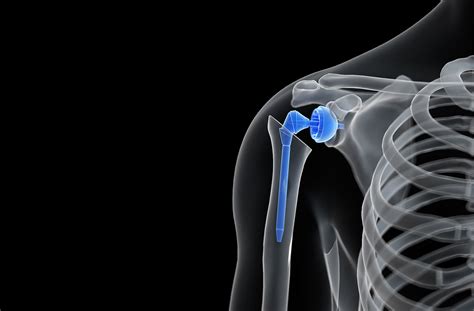

• Anatomic Total Shoulder Replacement: This is used when the rotator cuff tendons are healthy. The surgeon replaces the ball and socket with components that mimic the original anatomy.

• Reverse Total Shoulder Replacement: Designed for patients with severe rotator cuff tears or arthritis where the tendons are irreparable. In this case, the position of the ball and socket is reversed, allowing the deltoid muscle to take over the movement of the arm.

• Hemiarthroplasty: Only the humeral head (the ball) is replaced, while the original socket remains untouched. This is typically performed for specific fracture cases.